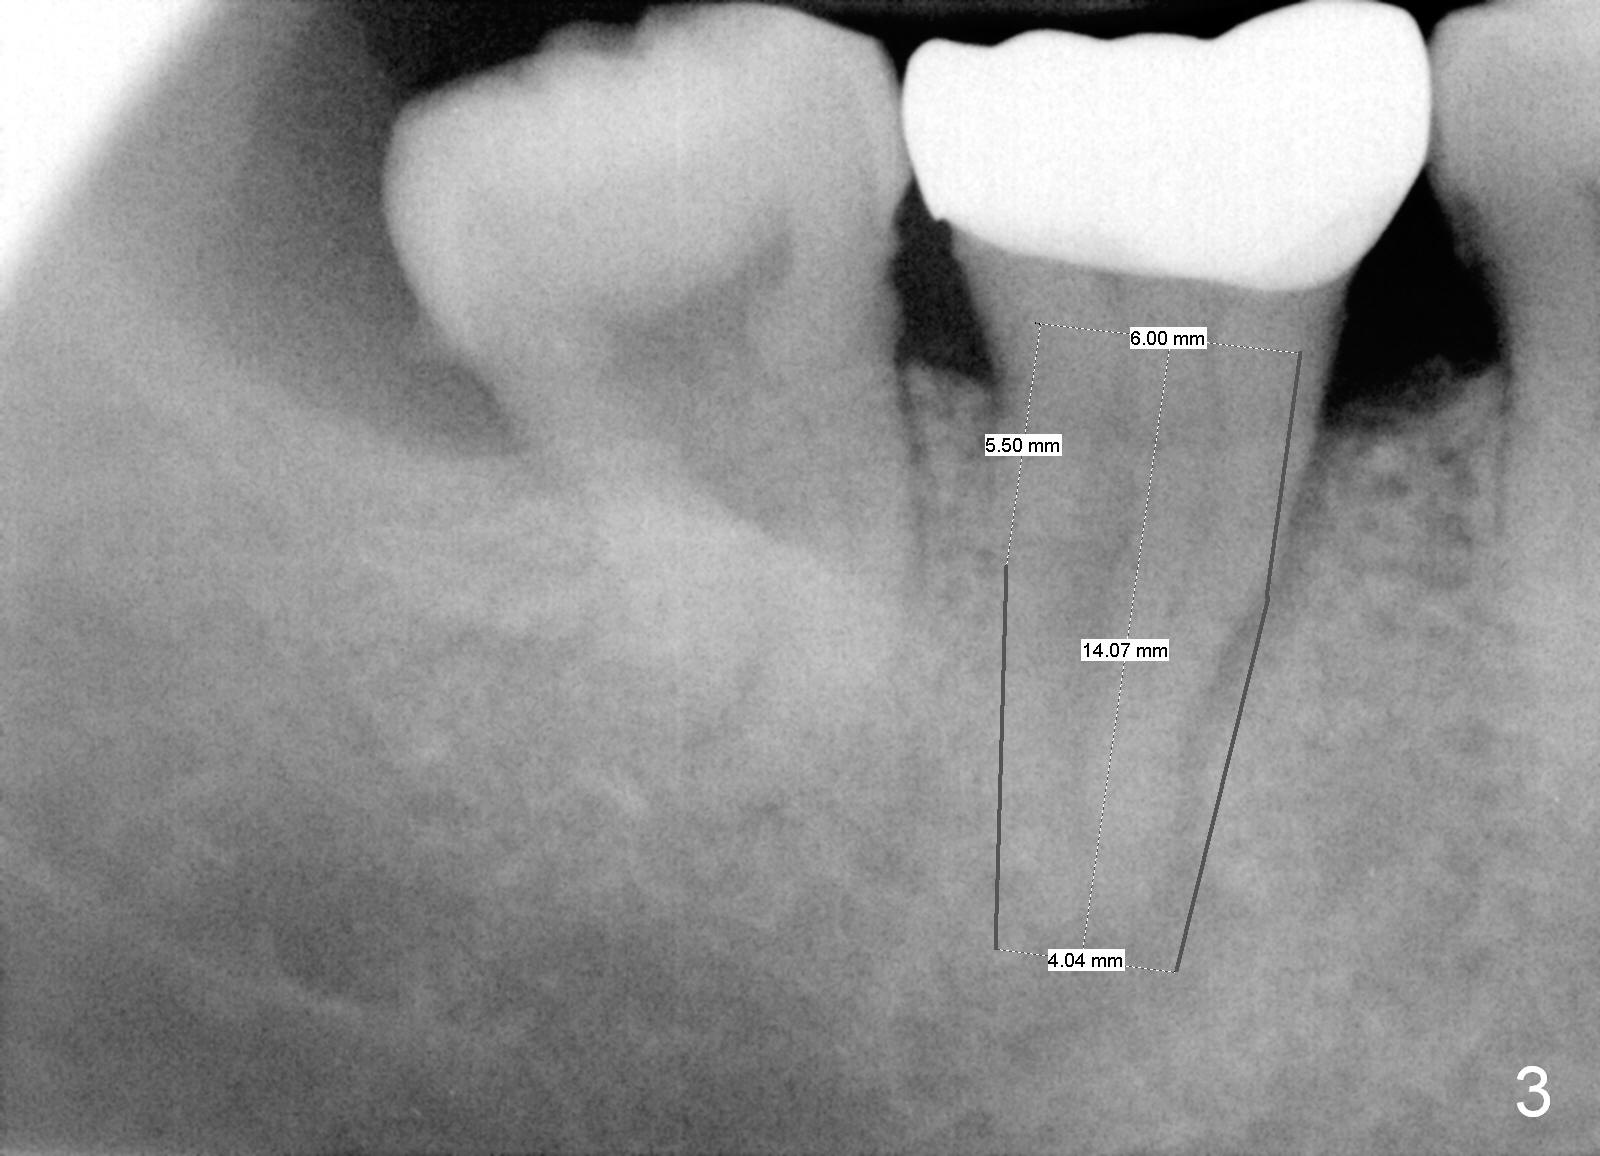

A 69-year-old lady has pain at #31. Because of curved and obliterated root canals (Fig.1,2), it is the better to extract the tooth and have an immediate implant. The roots are also long and narrow and close to the Inferior Alveolar Canal (Fig.1 yellow dashed line), whereas the canal is hardly recognizable in a 2nd PA (Fig.2 ?). For safety, taps are to be used for osteotomy (Fig.3).